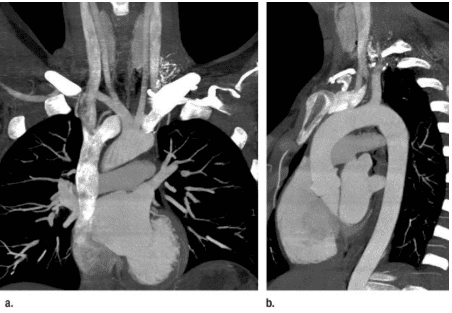

Triple-Rule-Out (viết tắt là TRO) là kỹ thuật chụp CTScan có thuốc cản quang dùng để khảo sát động mạch vành, động mạch chủ, động mạch phổi trong 1 lần chụp phim.

Kỹ thuật TRO thường dùng trong những trường hợp cấp cứu cần loại trừ các bệnh lý liên quan đến động mạch vành, động mạch chủ hoặc động mạch phổi, như thuyên tắc động mạch phổi, bóc tách động mạch chủ hoặc hẹp tắc động mạch vành.